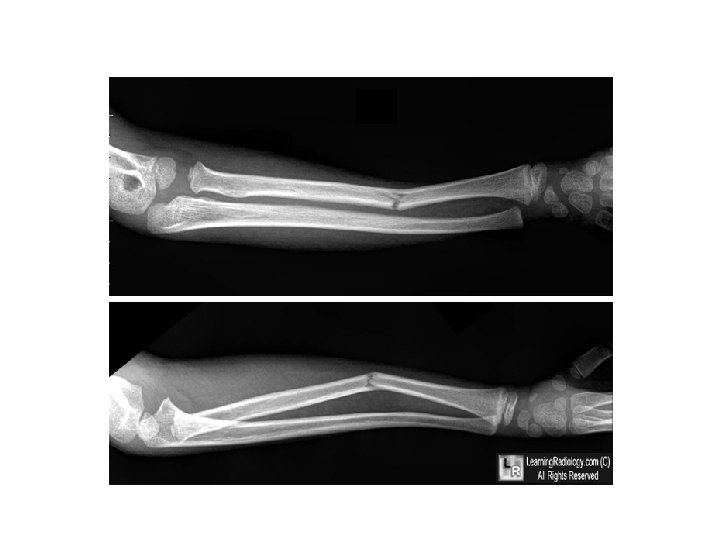

DESCRIBE TO ORTHO ATTENDING…

ANSWER • This one is a bit more challenging! • R midshaft tibia fracture displaced ½ the thickness of the bone without angulation; also there is bayonette appositioning of the fracture fragments • R midshaft fibular fracture with complete displacement and • Also comment if the fracture is open vs closed & neurovascular status